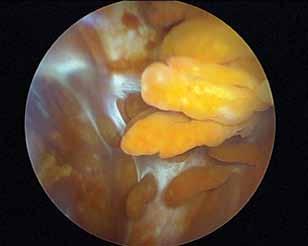

Fråga 2012-6 5p

Kvinna 57 årig tidigare frisk kvinna som inte tidigare har haft några problem med sina knäleder. En dag under vårens trädgårdsarbete känt smärtor i vänster knäled. Söker efter några dagar som jourfall då smärtorna snarast tenderar att öka. I status finner du lätt hydrops. Lätt rörelseinskränkning vänster jämfört med höger knäled. Lätt till måttlig ömhet medialt. Normal SR och CRP.

a. Differentialdiagnoser? (1p)

b. Hur handlägger Du patienten vid detta besök? (2p)

c. Hur utreder man ytterligare om patienten återkommer pga tilltagande besvär efter ett par veckor? (2p)

a. Troliga diagnoser är degenerativ meniskruptur/artros, spontan knäledsosteonekros eller insufficiensfraktur.

b. Noggrant knä- och höftstatus eventuellt slätröntgen och patientinformation om möjliga diagnoser. Smärtlindring och aktivitetsråd.

c. Vidare utredning med MR kan vara

indicerad speciellt för att kartlägga en eventuell osteonekros. Tc-scintigrafi kan också leda till rätt diagnos.